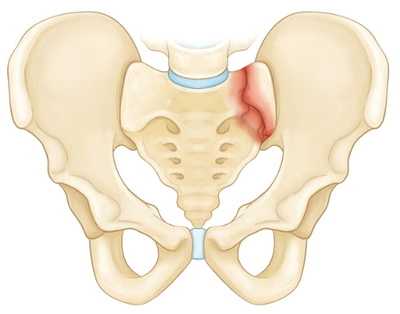

На рисунке — Изолированный перелом крестца

Стабильные переломы. Данный тип переломов обычно отличается наличием лишь одной линии перелома и сохранением анатомии тазового кольца. Низкоэнергетические переломы — это обычно стабильные повреждения. К стабильным переломам относятся следующие: